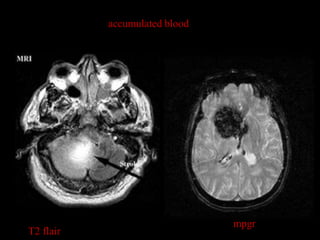

PATHOLOGIS

accumulated blood

mpgr

T2 flair

accumulated blood mpgr T2 flair